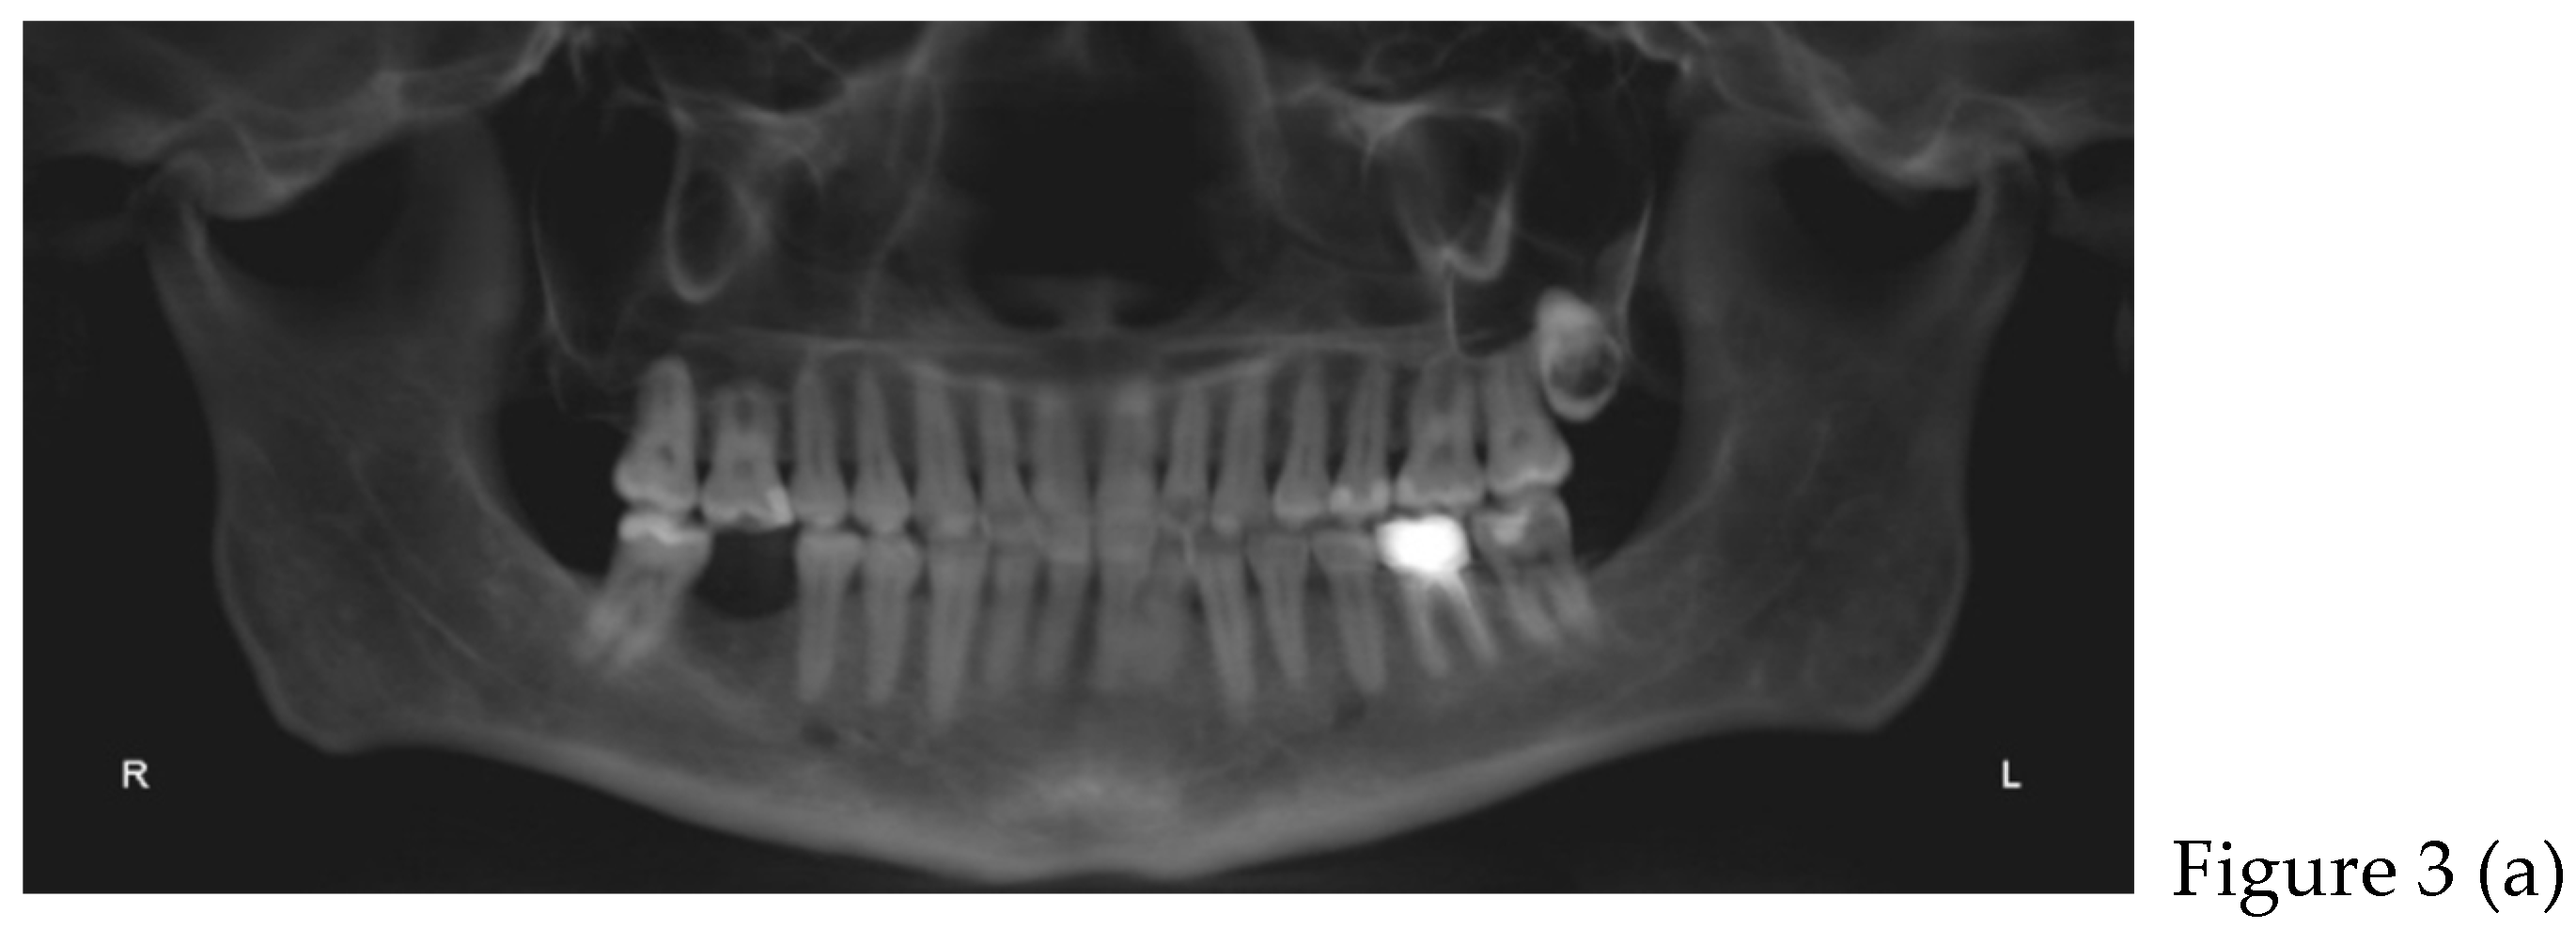

2.2. Cone Beam CT Analysis

| CBCT (t0) | |

| after 8 months | Retainers + CBCT (t1) + final photos |